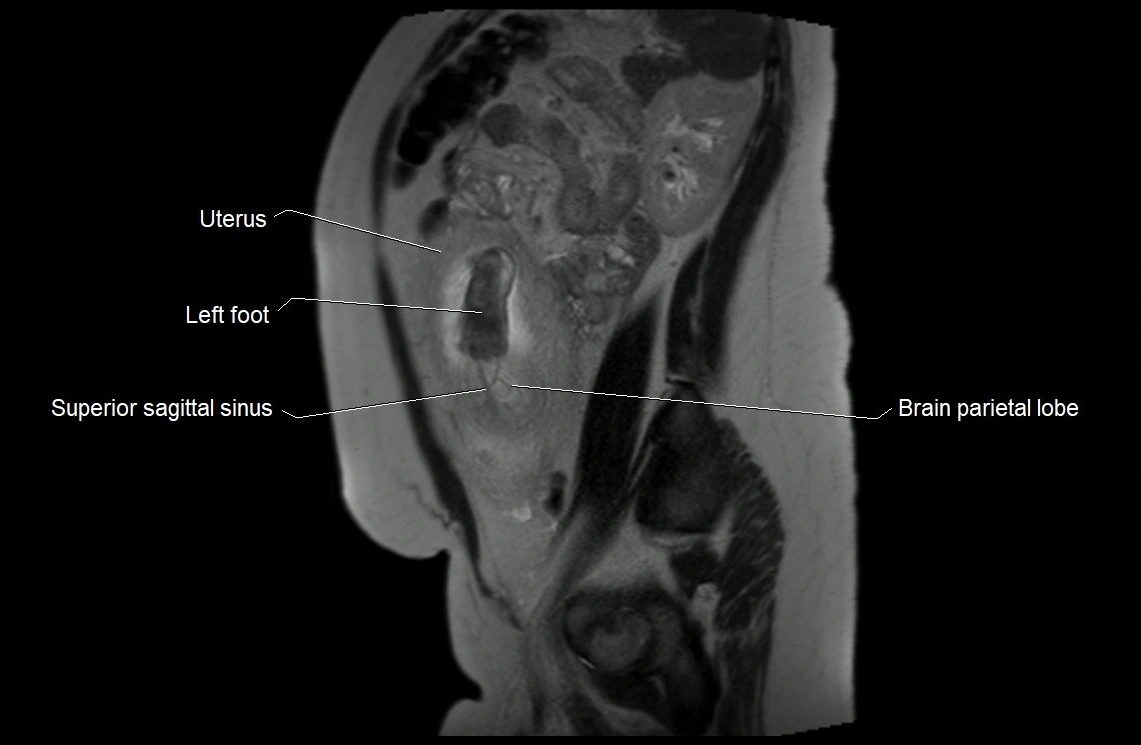

MRI Appearance

T2 HASTE (T2 GRE):

• Amniotic fluid shows very bright hyperintense signal

• Provides natural contrast against fetus and placenta

• Small particles (vernix) may appear as scattered hypointense foci within bright fluid

MRI image

image